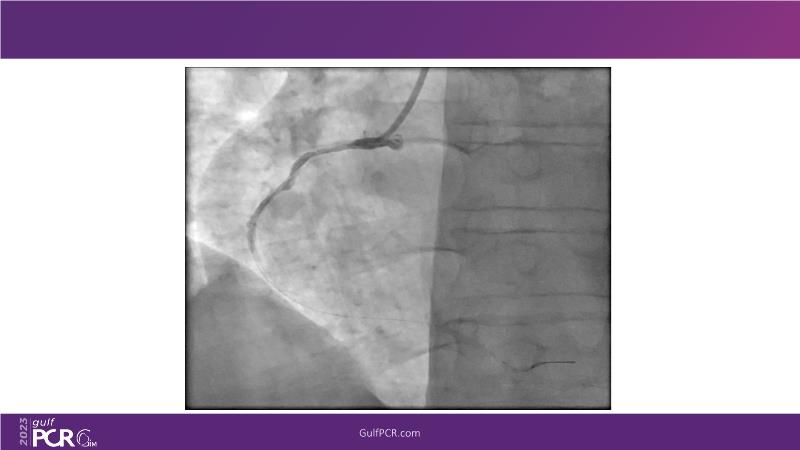

- To understand novel tools and techniques for effective management of bifurcation lesions and long diffused lesions using dedicated stenting solutions